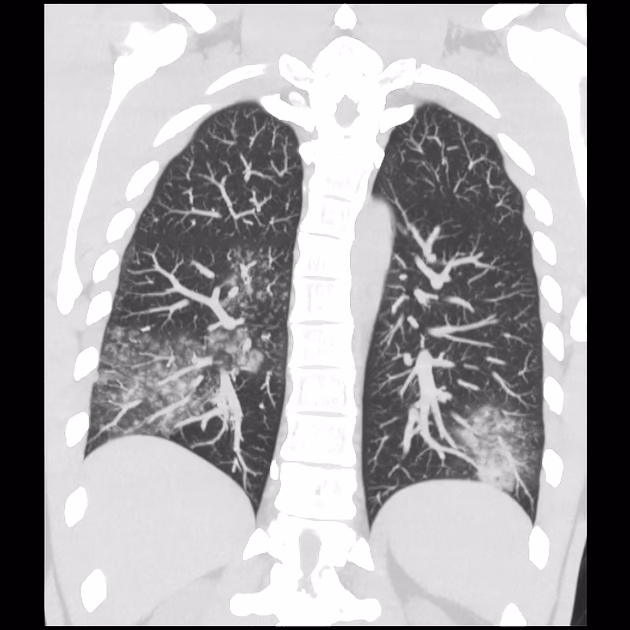

- Spredning til blodkarrene: Forskning tyder på, at C. pneumoniae kan rejse fra lungerne til blodbanen via inficerede immunceller, såsom monocytter og makrofager. Disse celler fungerer som en slags 'trojansk hest', der transporterer bakterien til arterievæggene.